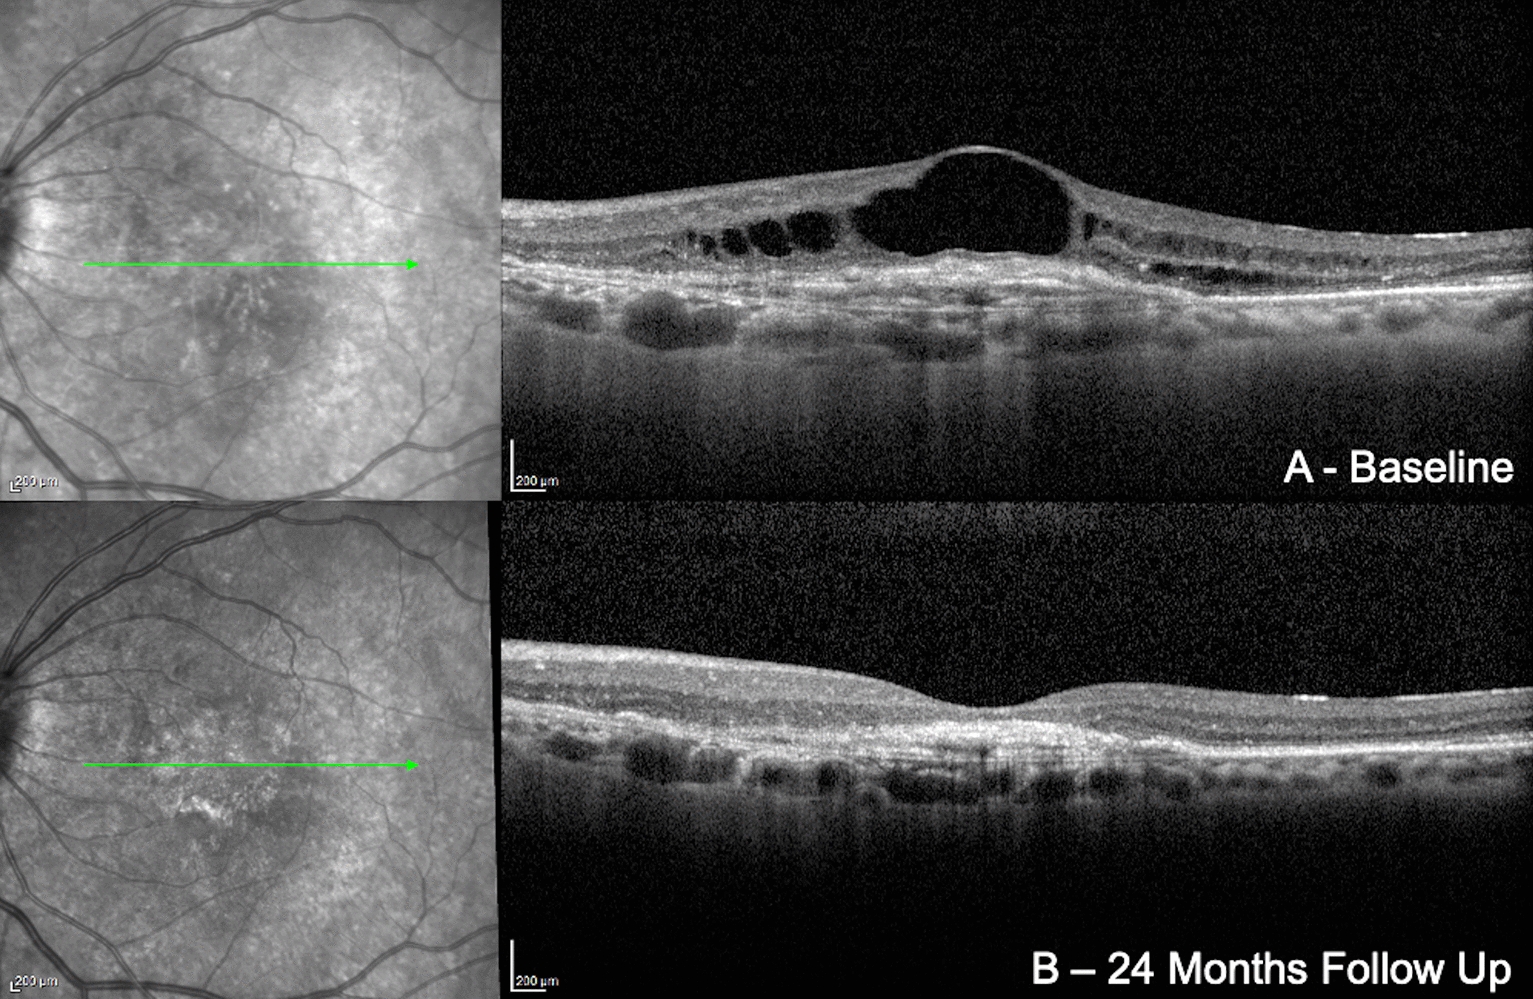

This study provides valuable insights into the long-term efficacy and safety of brolucizumab in patients with nAMD who were previously treated with other anti-VEGF agents. The findings contribute to the growing body of evidence on the role of brolucizumab in managing nAMD in real-world clinical practice, highlighting its capacity to achieve significant anatomical improvements while maintaining visual stability (Figs. 1, 2).

Fig. 1

Combined infrared reflectance and structural B-scan optical coherence tomography showing a type 1 exudative neovascular age-related macular degeneration. At baseline (a), intraretinal fluid (IRF) and an elevated retinal pigmented epithelium (RPE) with a double layer sign (DLS) are present, suggesting the presence of a neovascular membrane. At the 24-month follow-up visit (b)—after 7 brolucizumab intravitreal injections— it is noted that there is complete reabsorption of IRF and a reduction of the dimensions of the RPE. To note, the best-corrected visual acuity of the patient has not changed, remaining stable at 1 LogMAR. Despite the short duration of the disease (7 months) and the small number of intravitreal injections received at baseline (3), we noted that complete disruption of the external limiting membrane and ellipsoid zone were already present at baseline, possibly explaining the absence of visual improvement